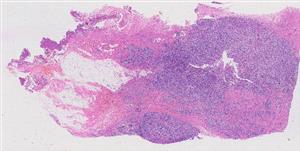

10519 |

左侧腹膜后肿块 |

女, 30岁, 2020年 09月,于外院行腹腔镜下盆腔肿物切除术,术后子宫... |

复旦大学附属肿瘤医院 |

有诊断 |